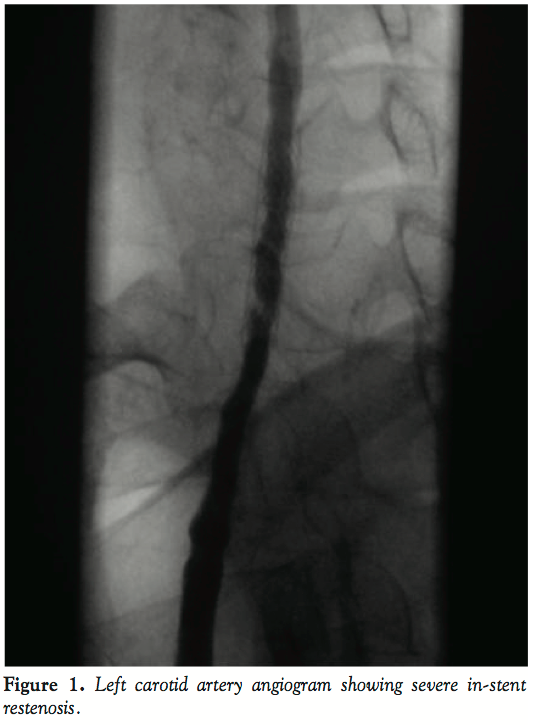

In December 2008, based on the ultrasound follow-up study in our institution, she was suspected to have significant in-stent restenosis in the distal part of the stented segment. Carotid angiography revealed severe restenosis in the distal Xact stent implanted in 2007 (Figure 2). The stent was well expanded and the stenosis was formed by progression of neointimal hyperplasia. According to this finding, a 4 mm x 28 mm drug-eluting coronary stent (Taxus, Boston Scientific) was deployed at the stenotic segment and post-dilated with a 5.5 mm balloon (Falcon Grande, Invatec) with residual narrowing of less than 10%.